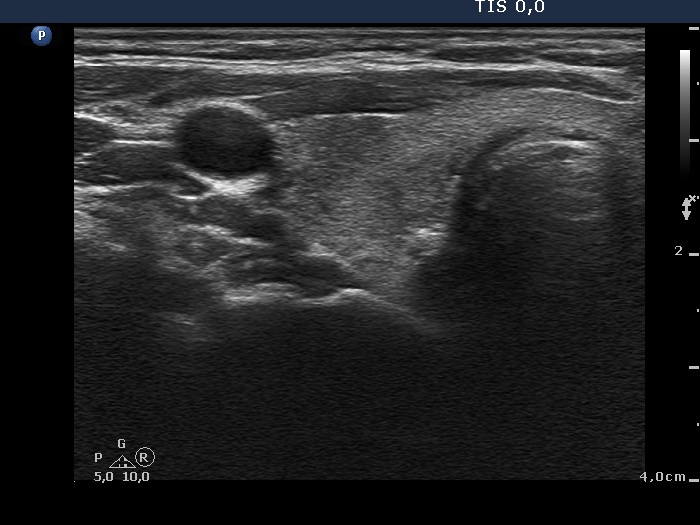

Follow-up 2 months after the first visit (3rd row of images):

Clinical presentation: Within 24 hours of the administration of 32 mg methylprednisolone, the neck complaints and subfebrility had stopped. When the patient reduced the dose to 8 mg daily for 2 weeks as suggested, the left lobe became sensitive. This tenderness has now been significantly reduced, but still persisted at times.

Palpation: The left lobe was tender on palpation.

Laboratory tests: TSH 1.62 mIU/L, FT4 9.97 pM/L, CRP 0.1 mg/L.

Ultrasonography: The right lobe decreased in size as did the extent of hypoechogenic areas in this lobe. The left lobe remained unchanged.

Suggestion: Discontinuation of steroid therapy. TSH in three months.

Follow-up 6 months after the first visit (3rd row of images):

Clinical presentation: The patient had no complaints.

Palpation: no abnormality.

Laboratory tests: TSH 2.06 mIU/L, FT4 13.3 pM/L, CRP 0.3 mg/L.

Ultrasonography: The pattern of the entire thyroid became almost completely normal. Only small hypoechoic areas were observed.

Suggestion: TSH in six months, in the event of pregnancy at once.